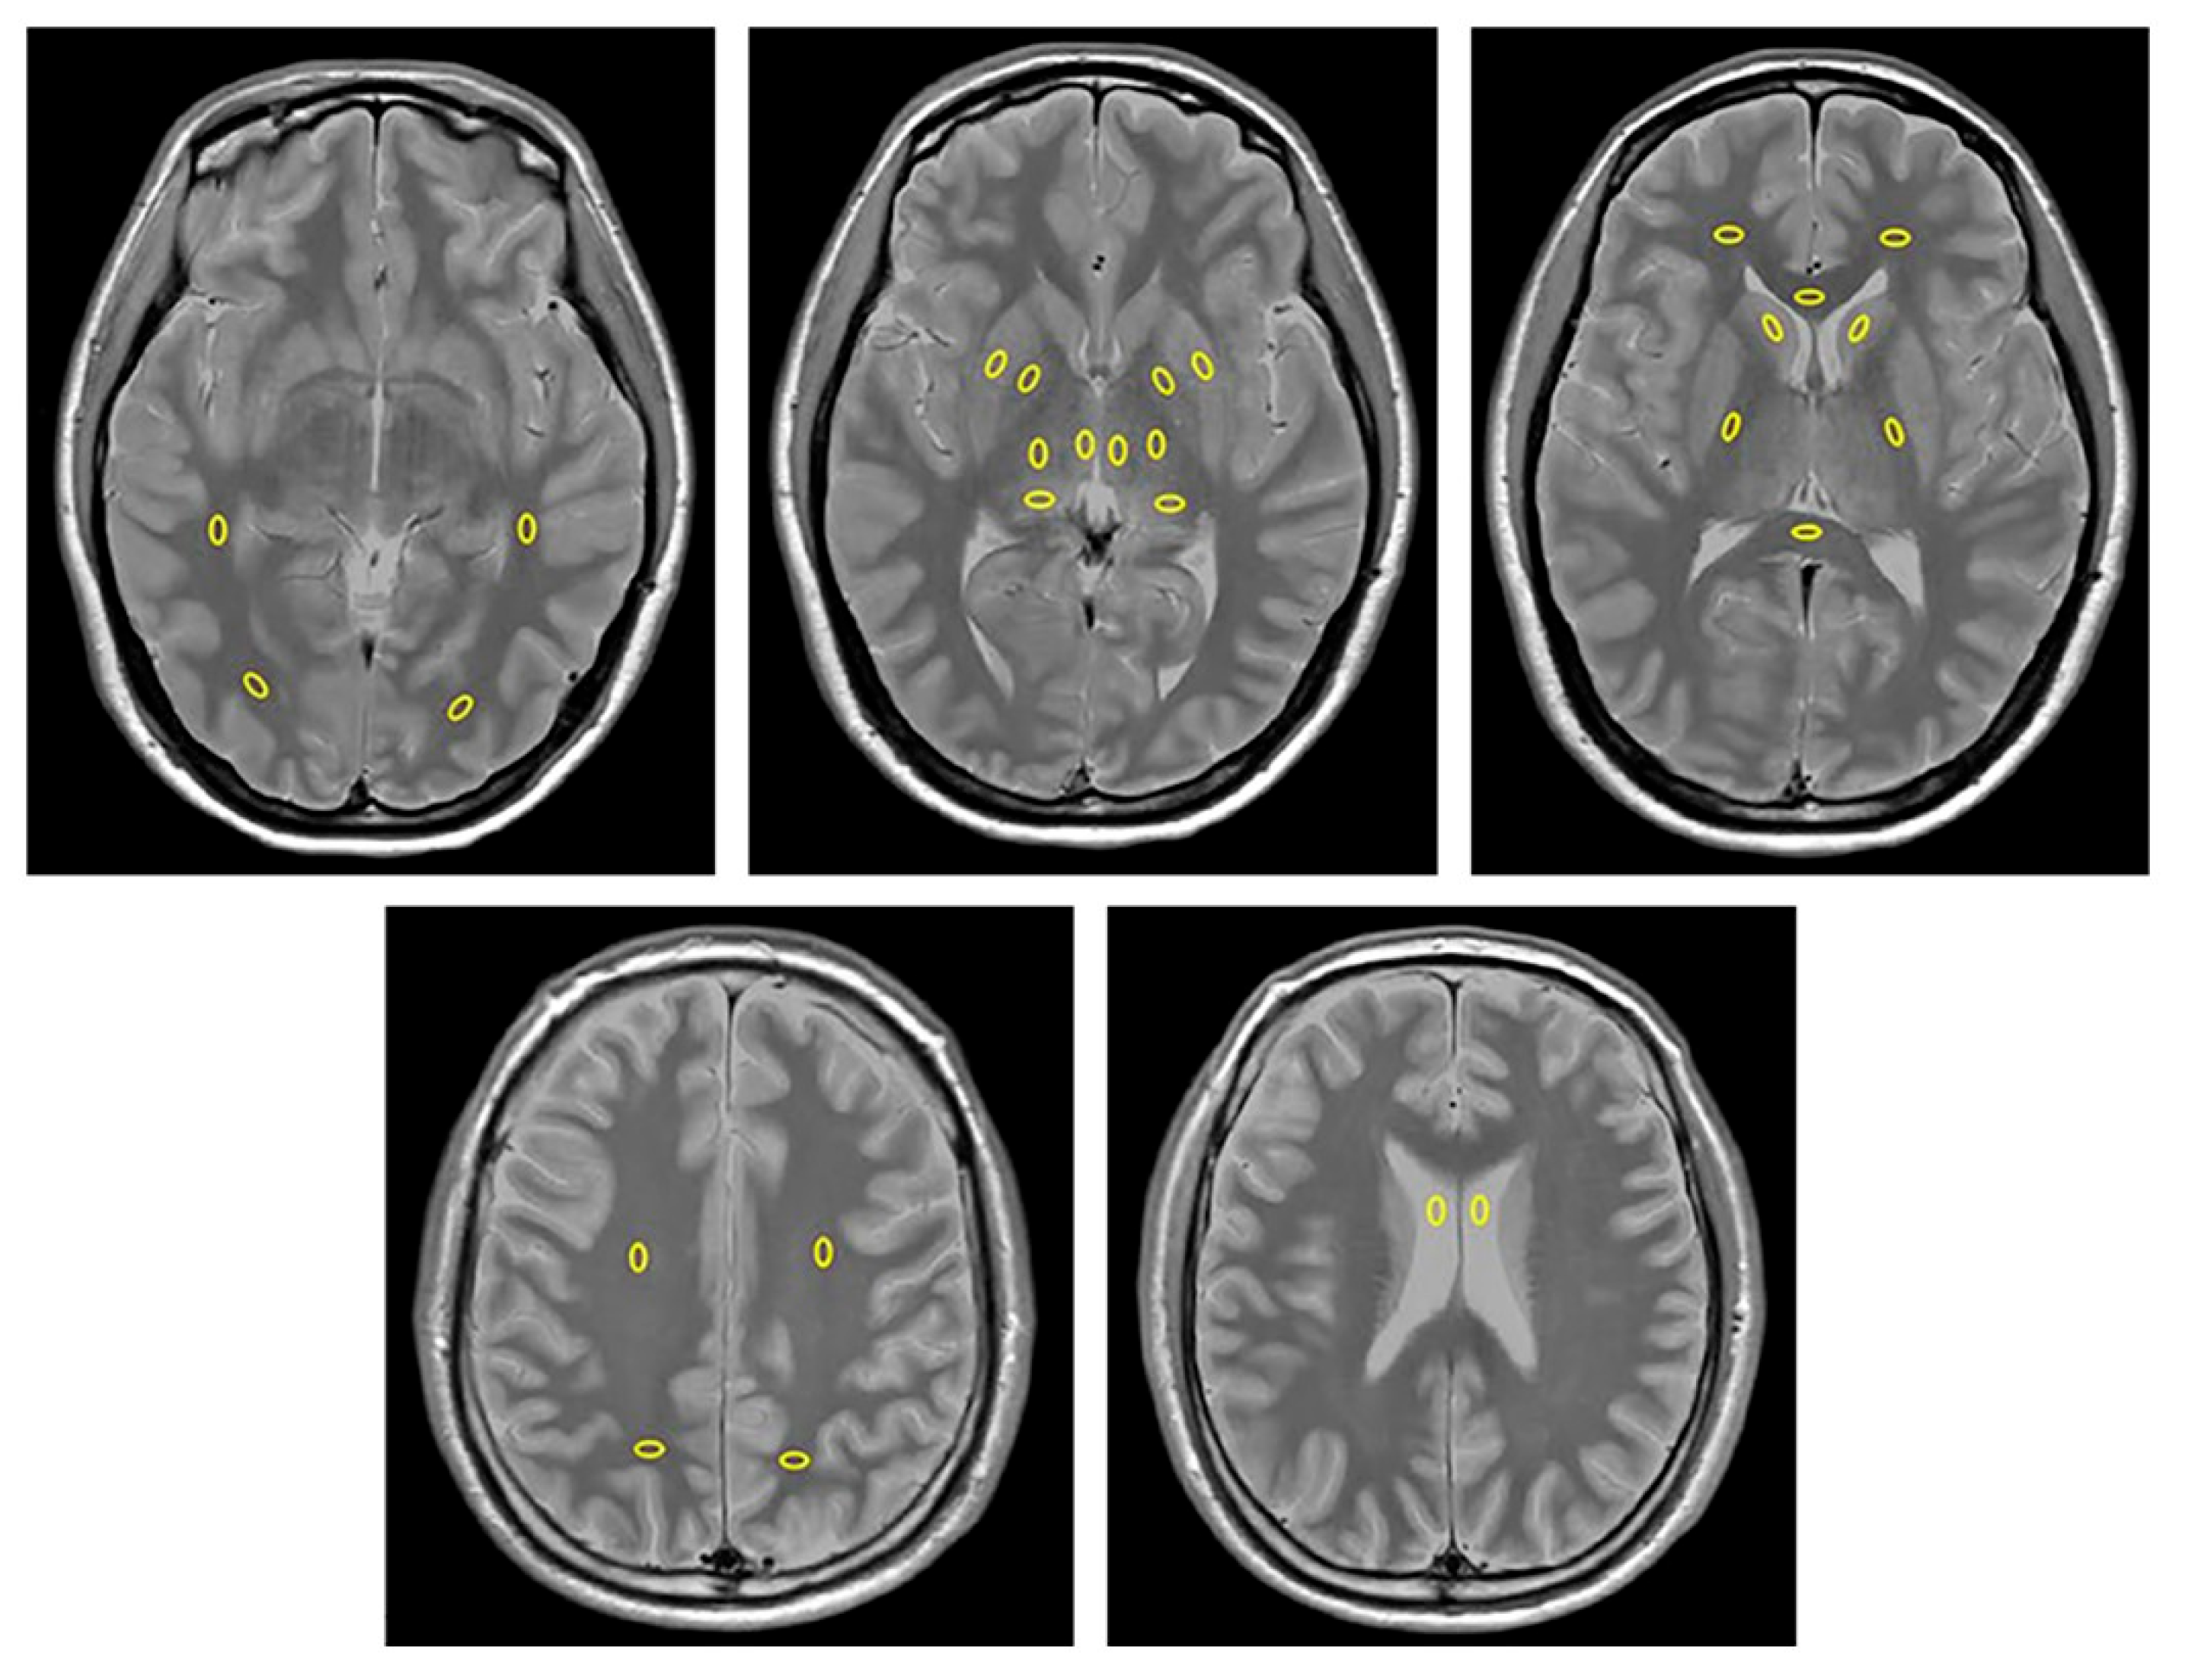

| White Matter (14 Regions) | Gray Matter (12 Regions) |

| Right frontal lobe | Right caudate head |

| Left frontal lobe | Left caudate head |

| Right temporal lobe | Right putamen |

| Left temporal lobe | Left putamen |

| Right occipital lobe | Right globus pallidus |

| Left occipital lobe | Left globus pallidus |

| Right parietal lobe | Right medial thalamus |

| Left parietal lobe | Left medial thalamus |

| Right centrum semiovale | Right dorsal thalamus |

| Left centrum semiovale | Left dorsal thalamus |

| Right posterior limb of the internal capsule | Right lateral thalamus |

| Left posterior limb of the internal capsule | Left lateral thalamus |

| Genu of the corpus callosum | |

| Splenium of the corpus callosum | |

| Cerebrospinal fluid (2 regions) | |

| Right lateral ventricle | |

| Left lateral ventricle |